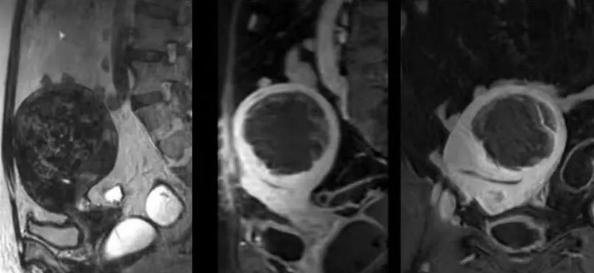

陳寶瑩主任首先給祝女士進行了詳細的盆腔磁共振評估,發(fā)現子宮肌瘤比較大,直徑七公分,類型和位置都適合做磁波刀治療。陳寶瑩主任立即為她制定了個性化治療方案,并為她完成幾項術前檢查。

治療當天,為緩解祝女士的緊張心情,陳寶瑩主任和她進行了充分溝通。術前準備就緒后,治療正式開始了。治療過程中,患者全程清醒,可以及時反饋治療感受。醫(yī)生也即時調整,確保整個治療安全有效,兩小時后治療順利結束,患者體驗度好。即時評估發(fā)現7公分的子宮肌瘤被消融掉80%,達到了預期目標。祝女士觀察一個小時后,沒有什么不舒服即回家了。